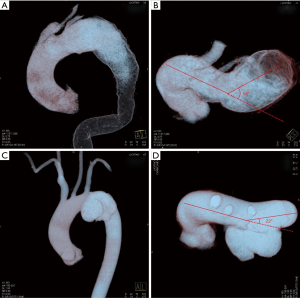

The most suited TEVAR-assistive technique was selected based on the following principles: F-TEVAR was the first option when aortic arch pathologies were located merely at the inner curve of the aortic arch, because a large-sized fenestration could be made to efficiently align the fenestration with the vascular branches. When pathologies involved the outer curve of the aortic arch and the diameters of the branch artery were large, F-TEVAR with a small-sized fenestration was used. Varieties of fenestrations are shown in Figure 1. When the angulation between the aortic arch and the descending aorta was hostile for orientation of the fenestration (Figure 2), and when branch artery dissection was present, C-TEVAR was employed. When the proximal intimal tear in the AD was located at the outer curve and very close to the branch arteries, the risk of an endoleak was considerable with the previous two techniques. In such cases, I-TEVAR was used.

Adequate understanding of the anatomical structure via the pre-operative CTA was essential for the success of orientation. Digital subtraction angiography (DSA) was performed and the diameters of vascular branches were measured to design a fenestration with comparable size to the target vessels. The proximal part of the aortic stent-graft was unsheathed in vitro, measured, and marked by a sterile pen. Then, the fenestration was fashioned by a scalpel alongside the spiral support strut beside the eight-shaped marker (Figure 1A). The edges of the fenestration were kept neat, and all fragments were carefully removed (Figure 1B). Then, the fenestrated stent-graft was carefully reassembled. Guided by an extra-stiff guide wire, the stent-graft was inserted into the descending aorta via femoral access. After confirming that the “8”-shaped marker and the spiral strut of the stent-graft were aligned with the target vessel, the stent-graft was carefully released. Then, angiography was performed to check the results (Figure 3A,B).